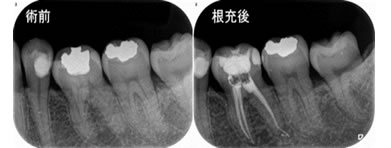

根管治療

虫歯の除去

虫歯菌によって汚染された歯髄歯の神経を除去します。

根管内の消毒

歯髄の管は部位や個人により本数が異なる上、形状も複雑ですが1本1本丁寧に消毒洗浄します。

薬の充填

歯髄がなくなった歯は再感染しやすいので薬を緊密に詰め、細菌の温床を除去します。

確認

根の先まで薬が入っているかレントゲンで確認します。

被せ物の作製

根管治療終了後、被せ物の型取りを行います。

※歯が割れた症例の8割が、根管治療後に被せ物の処置をしていない事が判明しています。